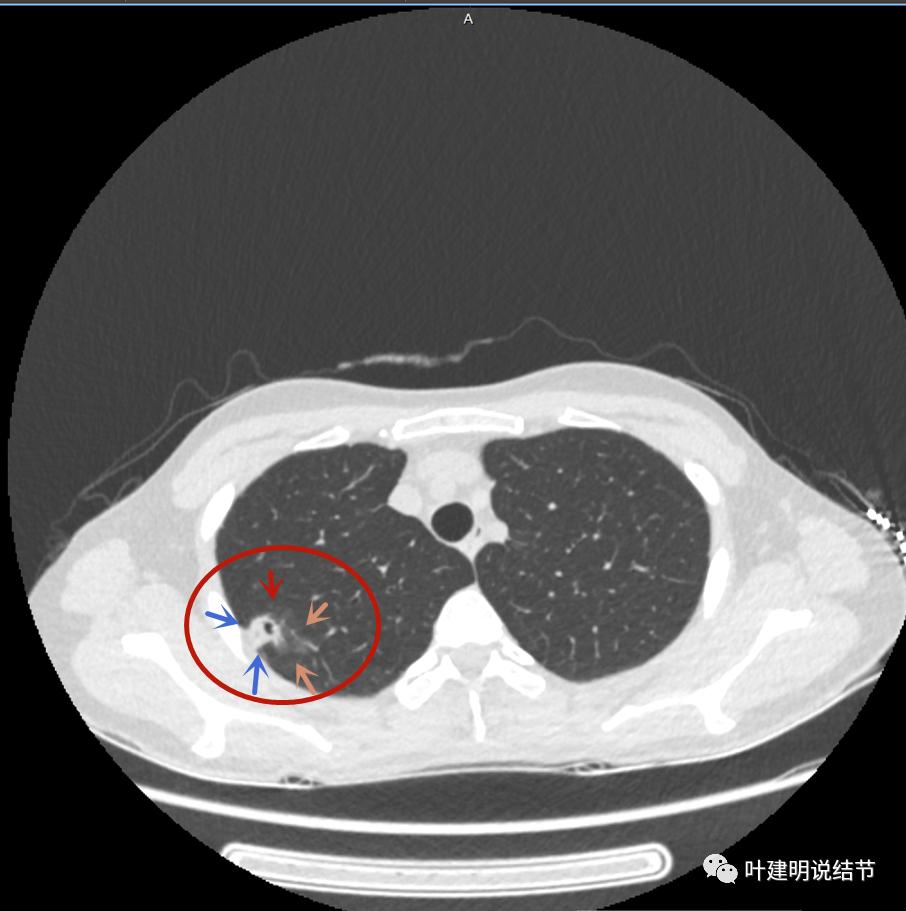

上图磨玻璃部分密度过低,且与正常肺组织界限模糊(砖色箭头),粉色箭头示囊壁密度过高的点状,蓝色箭头示邻近胸膜处的增厚

上图也像恶性,但整个囊壁的密度感觉过高了点,边缘磨玻璃淡、散且模糊,邻近胸膜有增厚

上图病灶的边相对比较光,没有毛刺征,邻近胸膜增厚